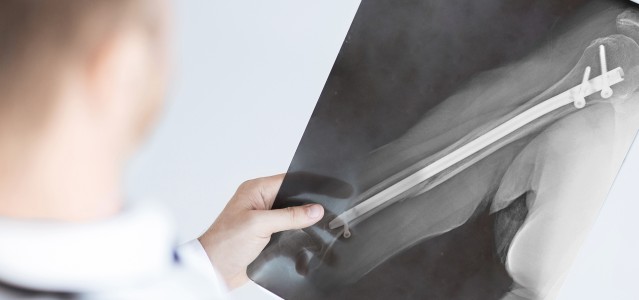

IM Nagel Röntgenbild

Beim chirurgischen Eingriff wird ein Loch in den Markraum eines gebrochenen Knochens gebohrt und ein langer intermedullärer Titan-Nagel in das Loch eingeführt. Der Nagel wird dann zum Zusammenhalt der gebrochenen Knochenstücke verschraubt, um erfolgreiche Heilung zu gewährleisten.